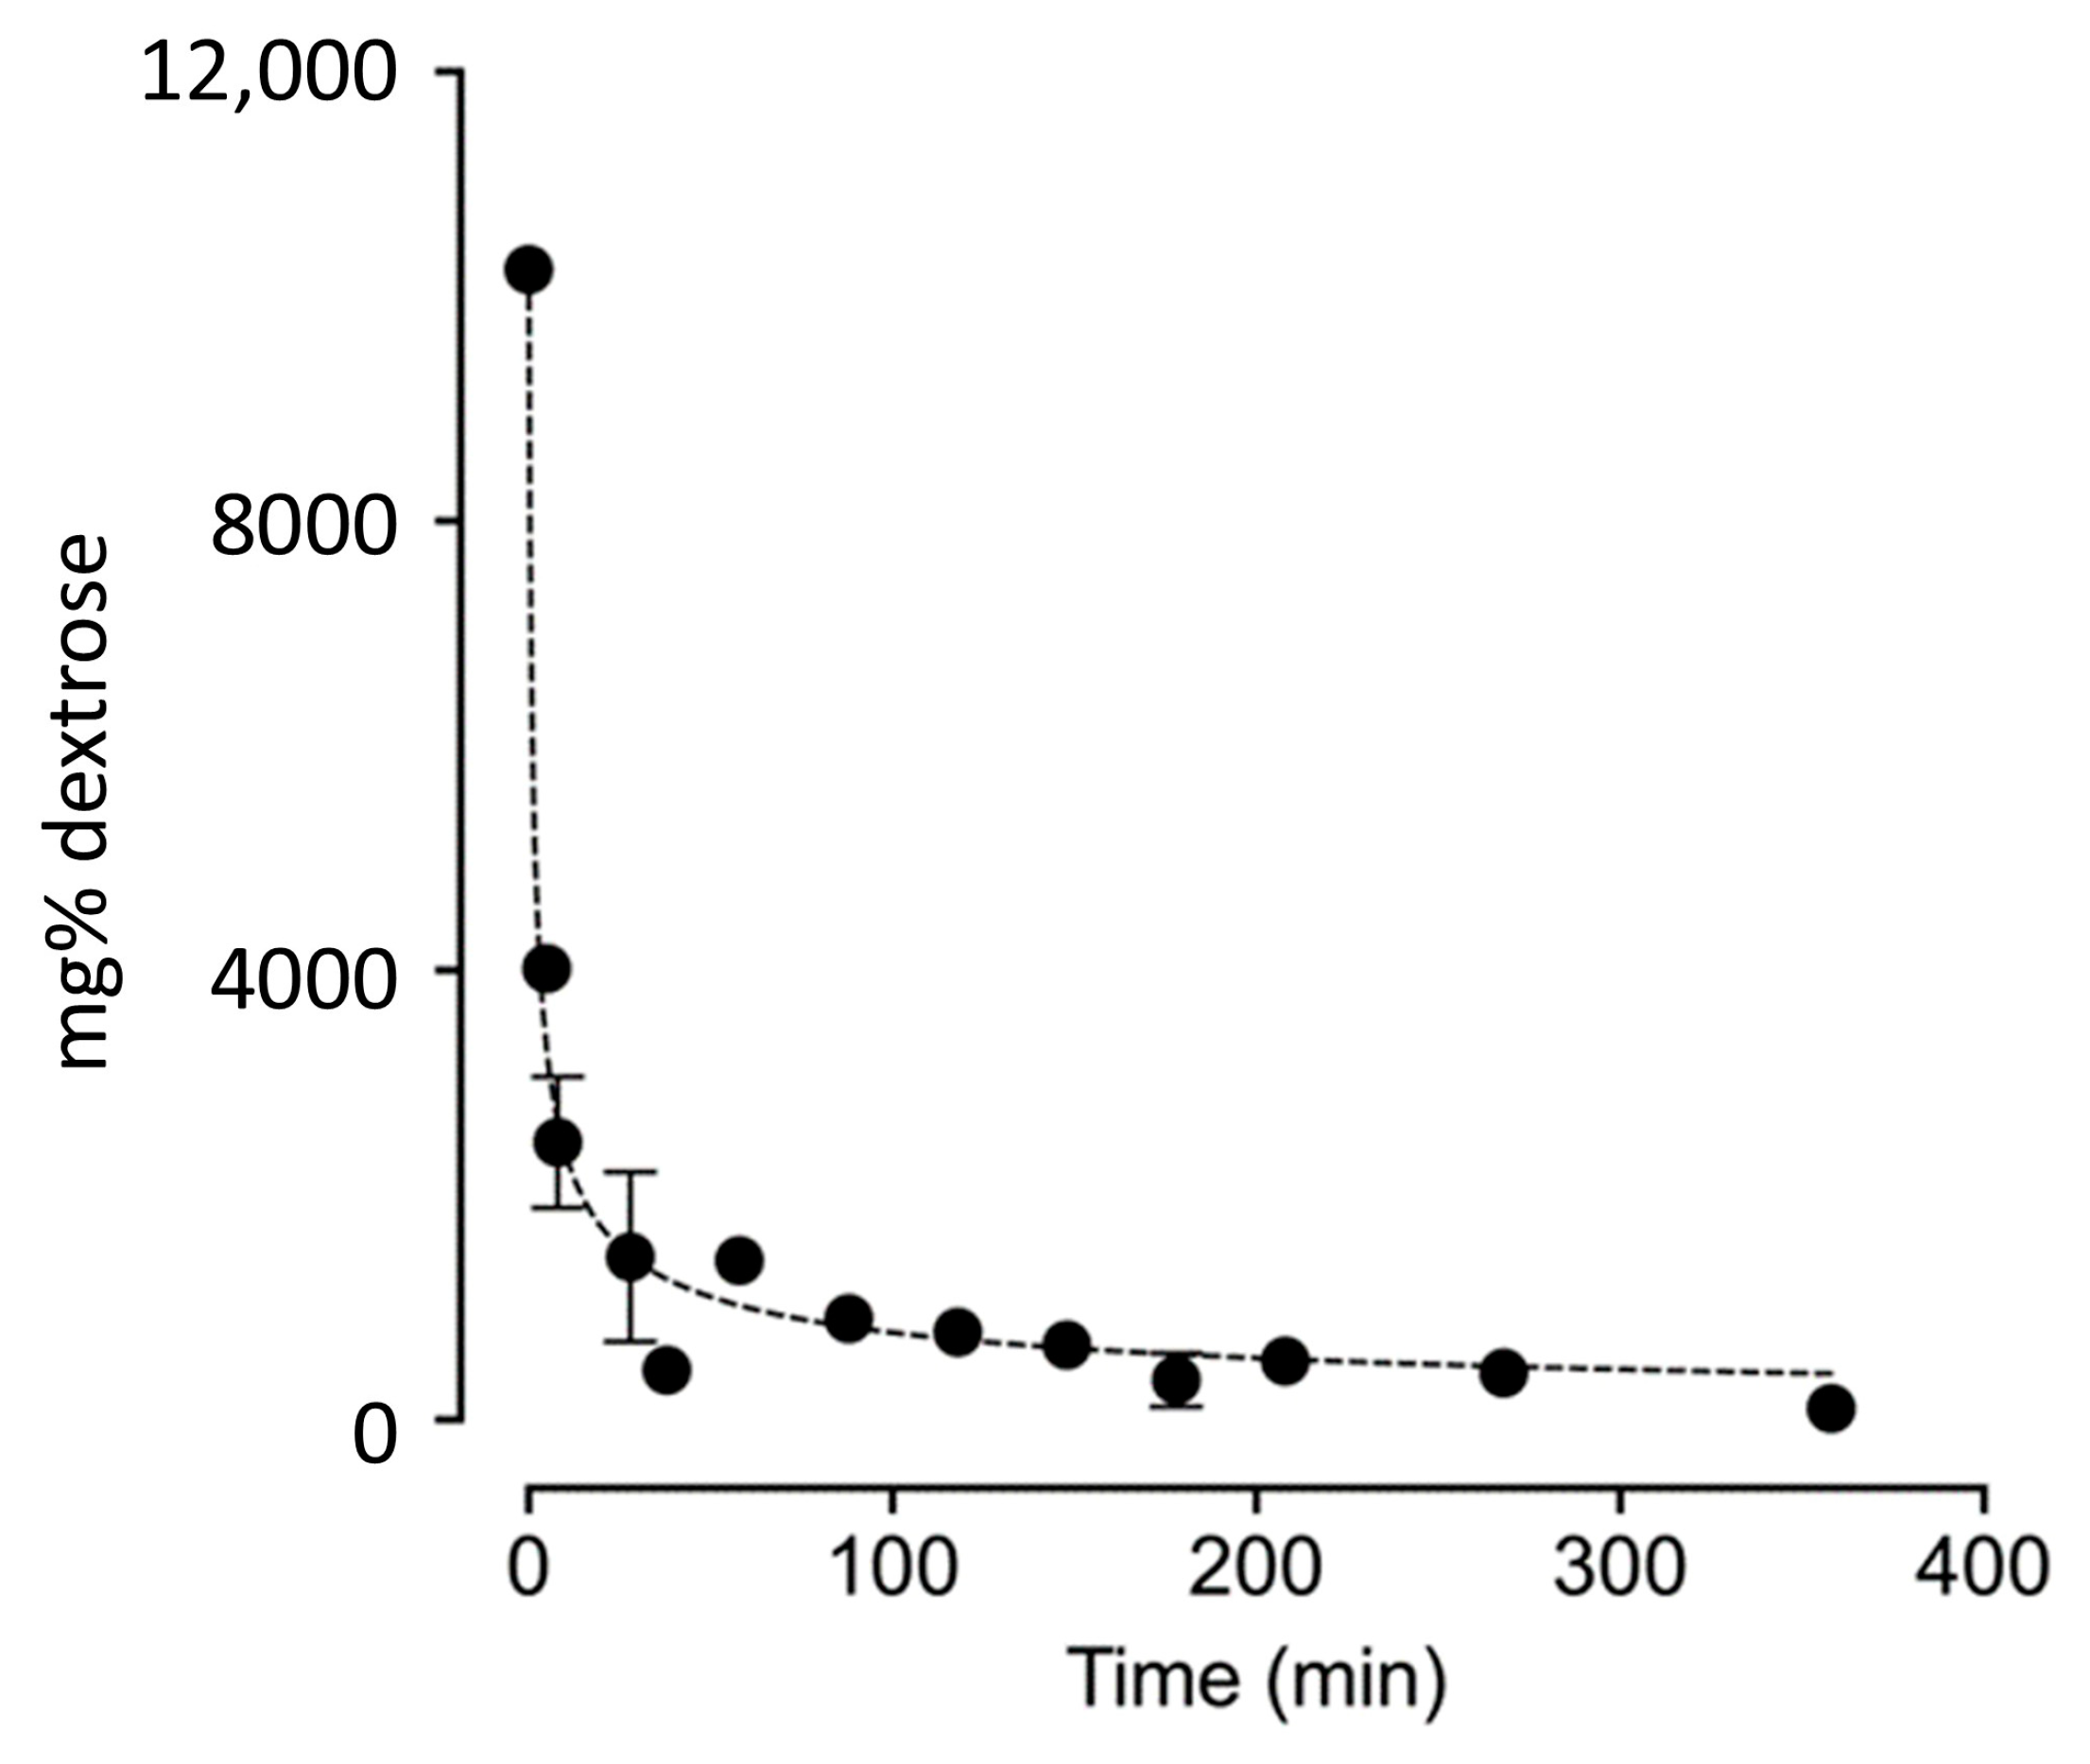

3.3. Dextrose Concentration Results from Trials 1–3

| Minutes After Beginning Injection | Trial 1 R Knee mg% (mM) | Trial 2 R Knee mg% (mM) | Trial 3 L Knee mg% (mM) |

|---|---|---|---|

| 0 Baseline synovial fluid dextrose (Estimated) | 100 (6) | 100 (6) | 100 (6) |

| 0 Injectate dextrose concentration | 12,500 (695) | 12,500 (695) | 12,500 (695) |

| 2 Estimated dilution effect 1 | 10,237 (641) | 10,237 (641) | 10,237 (641) |

| 7 | 4016 (223) | ||

| 10 | 2883 (160) | 2057 (114) | |

| 30 | 2303 (128) | 1195 (66) | 856 (48) |

| 60 | 1417 (79) | ||

| 90 | 899 (50) | ||

| 120 | 778 (43) | ||

| 150 | 667 (37) | ||

| 180 | 630 (35) | 258 (14) | 178 (9) |

| 210 | 523 (29) | ||

| 240 | 442 (25) | ||

| 270 | 416(23) | ||

| 360 | 102 (6) | 102 (6) |